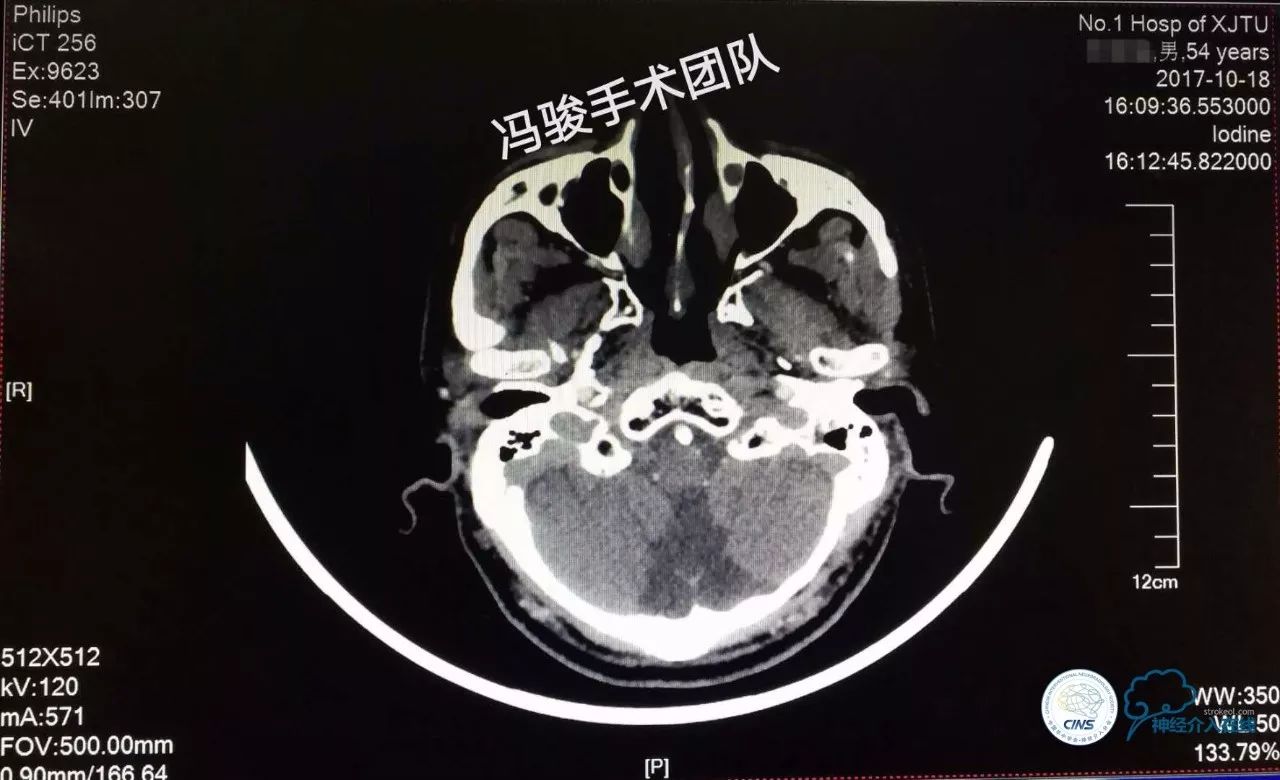

术后3月,复查头颅MRA,左椎动脉V4段支架血流通畅,患者无不适,继续双抗+强化他汀,随访。

术后1年余,复查头颅CTA,左椎动脉V4段支架血流通畅,患者无特殊不适,效果满意,嘱继续随访。汇报完毕!